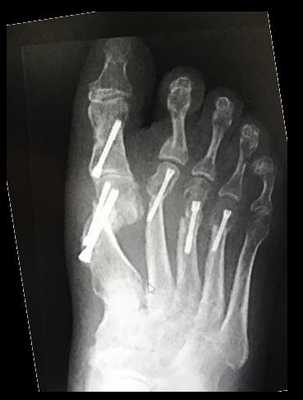

Косточка на большом пальце ноги, тяжёлый случай

Часто пациенты обращаются на запущенных стадиях заболевания, когда происходит не только смещение большого пальца кнаружи с образованием «косточки» в области головки первой плюсневой кости, но также появляется молоткообразная деформация 2-3-4 пальцев, внутреннее отклонение 5 пальца, появление косточки в области головки 5 плюсневой кости, возникновение болей под головками 2-3 плюсневой кости.

Все эти деформации требуют дополнительных вмешательств и значительного расширения объёма операций.

Клинический пример, пациентке 75 лет, деформация у неё начала прогрессировать с 20 летнего возраста. Что же произошло за это время?

- Первая плюсневая кость отклонялась всё дальше кнутри, а первый палец соответственно отклонялся кнаружи

- Сесамовидный гамачок вывихнулся и оказался между 1 и 2 плюсневыми костями

- Нагрузка постепенно полностью ушла с первого пальца и перешла на головку второй плюсневой кости

- Произошло разрушение капсулы 2 плюсне-фалангового сустава, второй палец вывихнулся кверху

- Нагрузка частично перешла на 3-4 плюсневые кости, и это вызвало их перегрузку и формирование молоткообразной деформации 3-4 пальцев

В такой ситуацией задачей хирурга является восстановление нормальной параболы головок плюсневых костей в продольной и в поперечной плоскости.

Для этого может быть использован целый арсенал различных остеотомий.

Для 1-й плюсневой кости это может быть остеотомия по типу слайд даун, экстремальная скарф остеотомия со значительным укорочением, проксимальная клиновидная остеотомия, артродез 1 плюсне-клиновидного сустава, двойная остеотомия (проксимальная и дистальная)

В конечном итоге использовал скарф, но при таком узком диафизе и такой степени деформации добиться полноценной коррекции на скарфе невозможно.

После коррекции первого луча необходимо решить вопрос со вторым перекрещенным пальцем. Для устранения вывиха в 2 плюсне-фаланговом суставе необходимо очень сильно укоротить 2-ую плюсневую кость. И эту задачу можно решить при помощи косой или поперечной остеотомии с резекцией костного блока необходимого размера. Я выбрал поперечную остеотомию с резекцией примерно 1 см участка диафиза 2 плюсневой кости без фиксации.

Молоткообразная деформация 3-4 пальцев устраняется за счёт уменьшения нагрузки на головки 3-4 плюсневых костей (остеотомии вейль, хелал, ДММО) я выбрал ДММО как самую быструю, простую и эффективную.

2-й палец в ригидной молоткообразной деформации, поэтому кроме артропластической резекции ничего в голову не приходит.

И Акин для дополнительной коррекции наружного искривления 1-го пальца и контроля его ротации.

Через 12 недель отёк в большей степени регрессировал. Наружное искривление 1 пальца недокорректировано, молоткообразная деформация 2-го пальца устранена. Поперечный свод восстановлен

Нормальная парабола головок плюсневых костей восстановлена в обеих плоскостях. Определяется консолидация 2-3-4 плюсневых костей несмотря на отсутствие фиксации. Первая плюсневая кость находится в не оптимальной позиции.